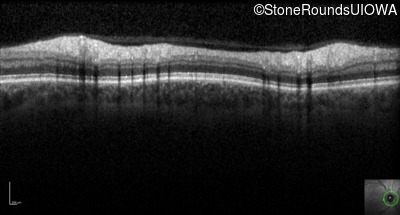

Optical Coherence Tomography - Right - 20/400 sc

Exemplar / OCT Stack